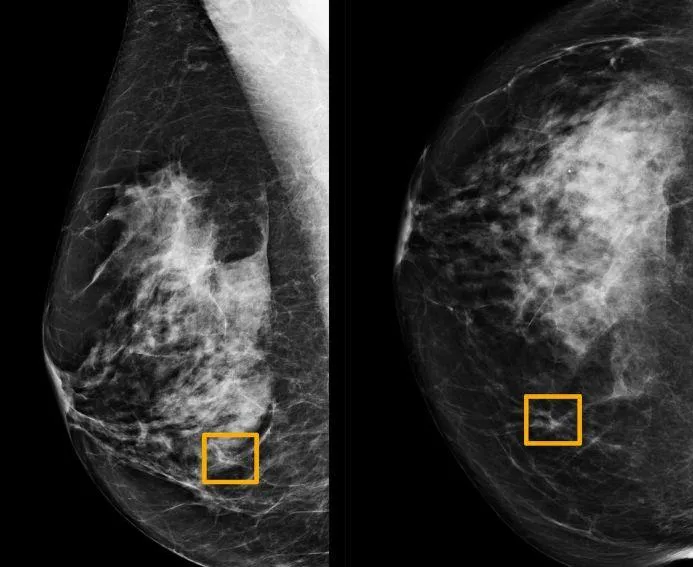

النظام يكشف الإصابة بسرطان الثدي استناداً إلى التصوير بالأشعة السينية (رويترز)